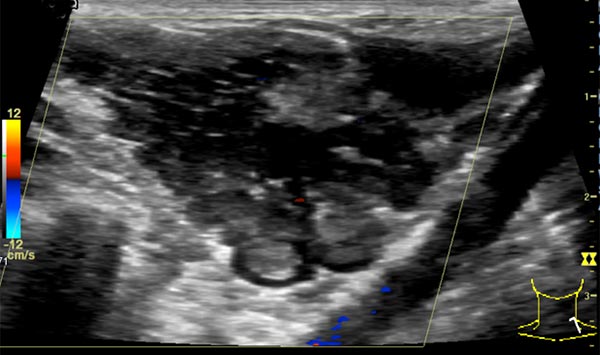

In color-coded duplex sonography, the venous malformation is also clearly delineated. Because it is a slow-flow lesion, it shows virtually no perfusion here. Flow through the lesion is minimal. Very few color signals are found outside the venous malformation, despite the selection of low pulse repetition frequency.

In quantitative contrast-enhanced sonography (CEUS), several areas of interest are continuously measured with regard to their contrast enhancement for perfusion analysis of the venous malformation. The values measured here also show the classic character of a slow-flow lesion.